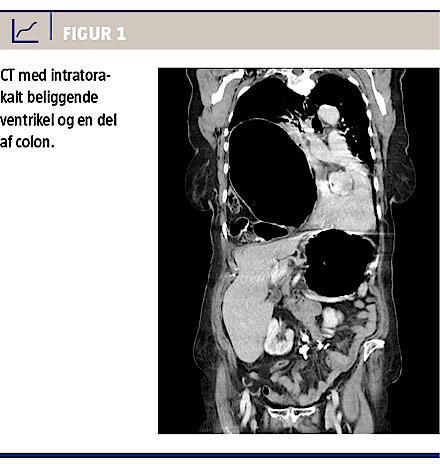

En 79-årig kvinde blev i februar 2012 indlagt elektivt til operation for et stort symptomgivende diafragmahernie. Defekten i diafragma mentes at være opstået ved et traume i forbindelse med en trafikulykke i 1988. Hun havde siden været indlagt flere gange

med herniering af ventriklen gennem defekten i diafragma, senest en måned forud for dette forløb. Symptomerne var åndenød, svære øvre abdominalsmerter og opkastninger. En CT viste en intratorakalt beliggende ventrikel og en del af colon (Figur 1). Man behandlede tilstanden konservativt med ventrikelsonde, og hun blev udskrevet til planlagt operation en måned senere. Der blev foretaget laparoskopisk procedure, hvor man i diafragma fandt en 10 × 5 cm stor defekt, som var lokaliseret anteriort og til venstre for hiatus oesophageus. Der var herniering af ventriklen, højre del af colon og en større del af tyndtarmen i højre hemithorax. Indholdet kunne umiddelbart reponeres. Defekten i diafragma dækkede man med en Bard Composit E/X-meche (10,2 × 15,2 cm) og fæstnede den dels med Protacs (5 mm), dels med Goretexsutur. Grundet vævstensionen og defektens alder var det ikke muligt at adaptere kanterne med sutur alene.